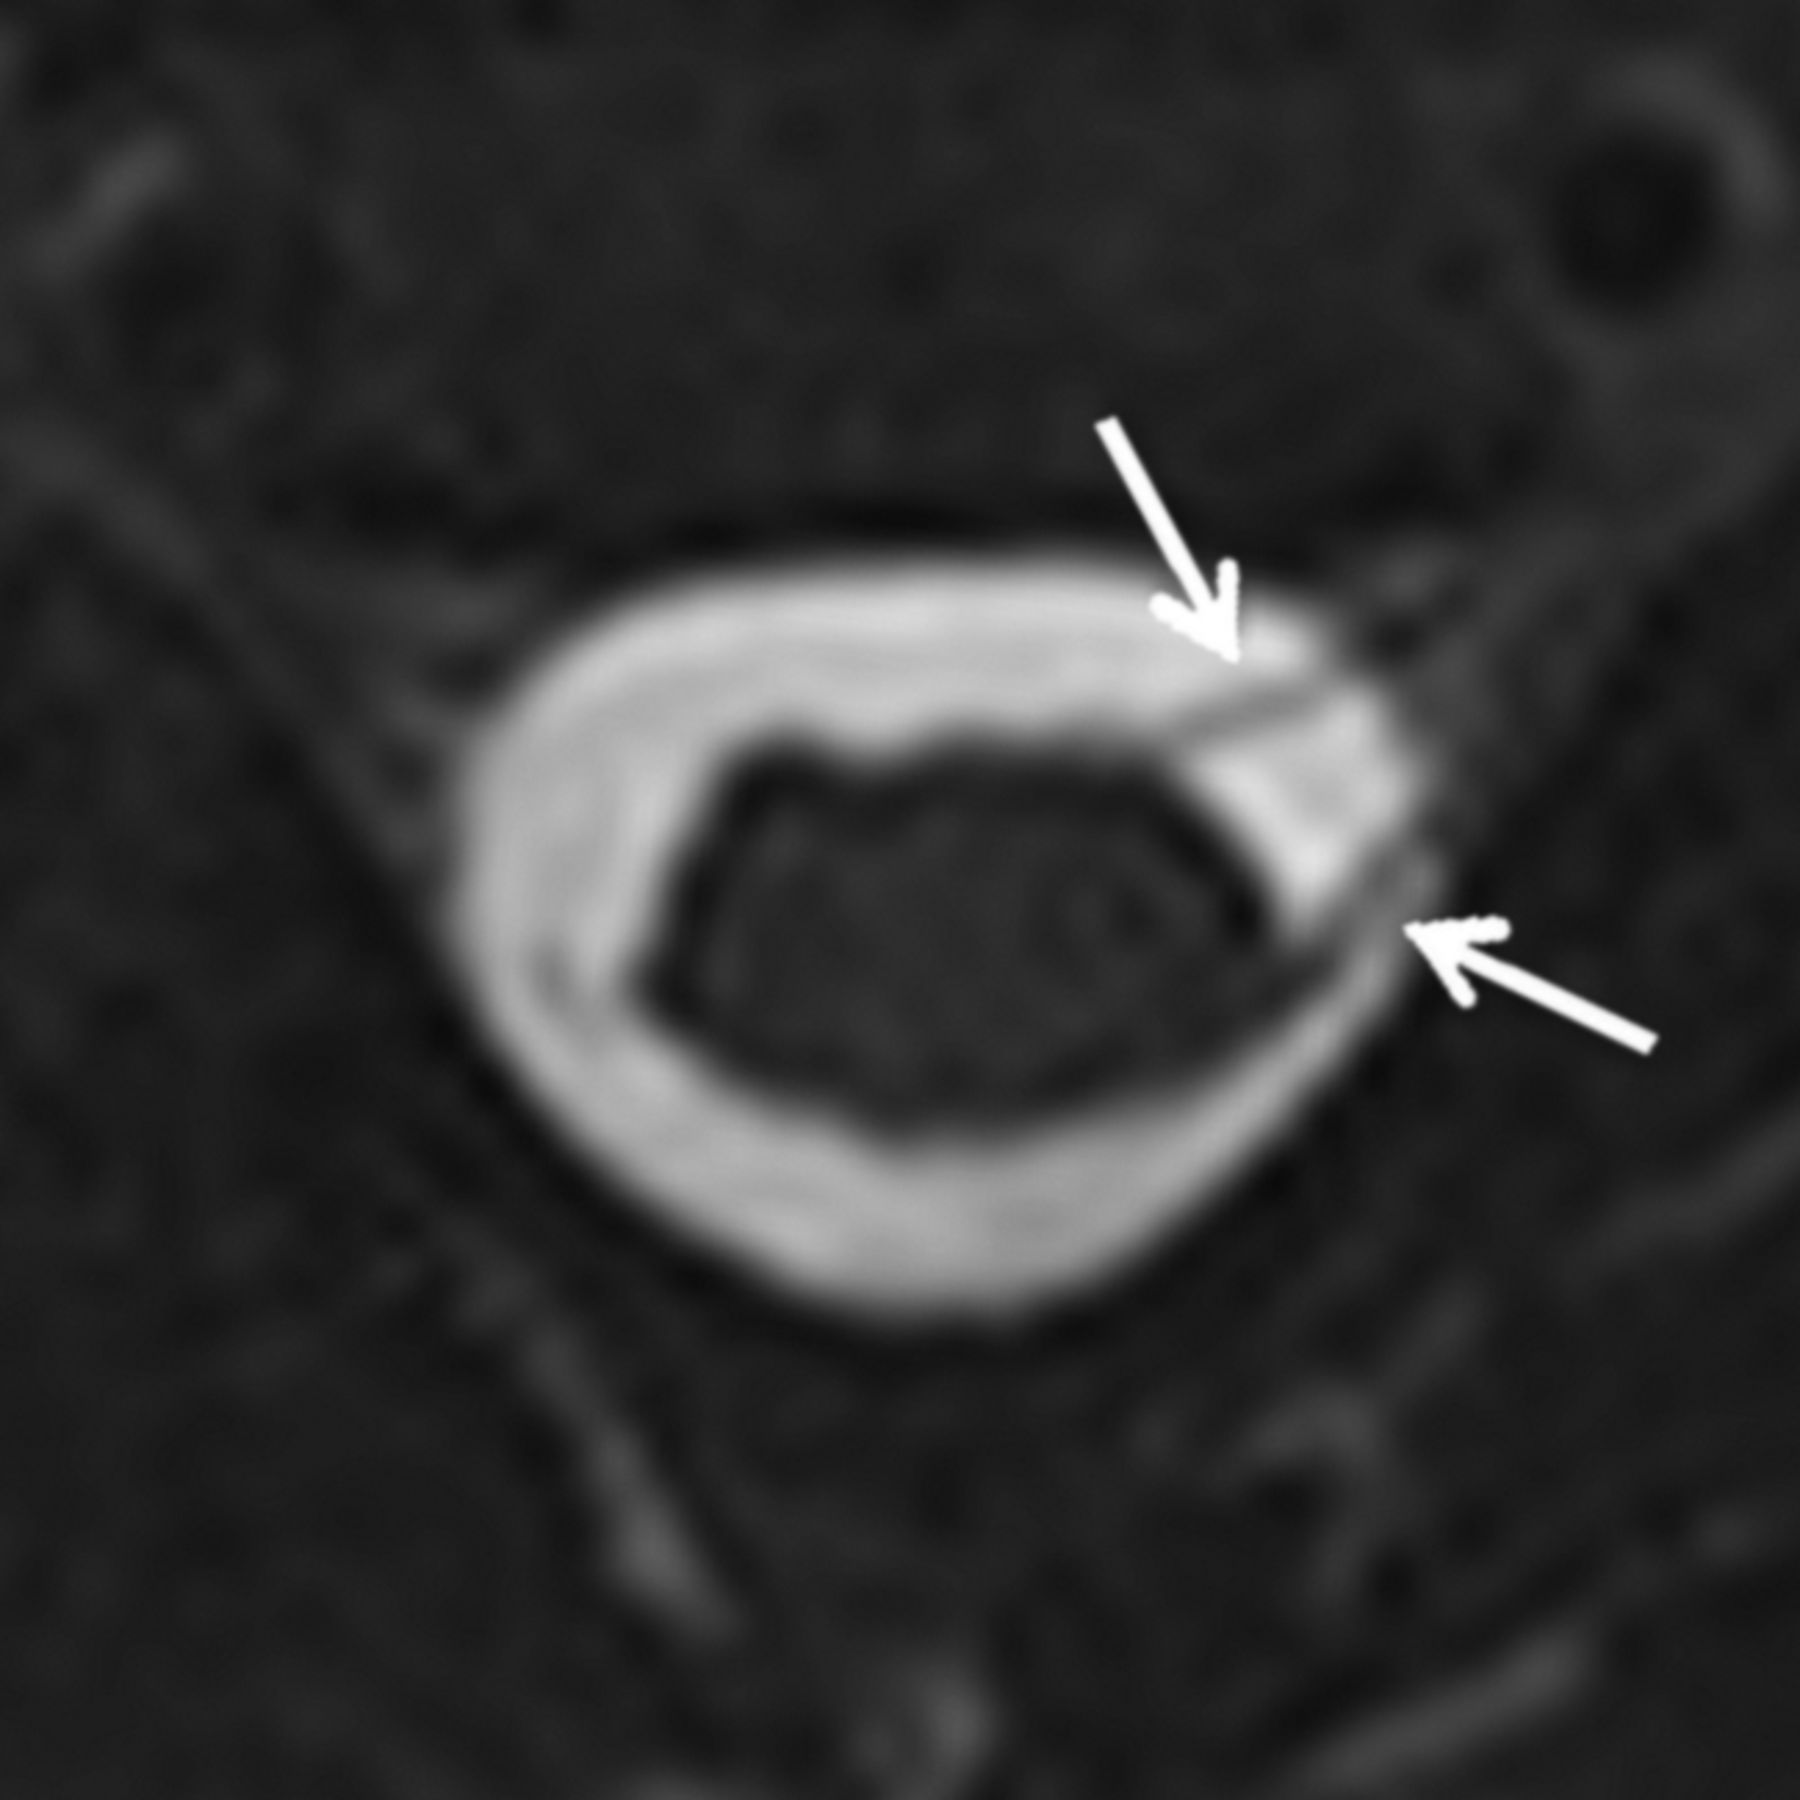

Two pediatric radiologists (with 7 and 8 years' experience, respectively) independently evaluated each imaging study and rated each root level from C5 to T1 according to the system in Table 1. Discrepancies were resolved by consensus analysis. Findings A and B (Figs 1 and 2) have previously been used as predictors of nerve root avulsion in infants.14 Finding C (Fig 3) has been described as a predictor in adults.19 Findings D and E (Figs 4 and 5) have been suggested to indicate partial nerve root avulsion.12

Left parasagittal (A) and axial (B) images from a CT myelogram demonstrating a left-sided pseudomeningocele at T1. A thin linear filling defect within the pseudomeningocele continued centrally to the cord and was interpreted as an intact nerve root.